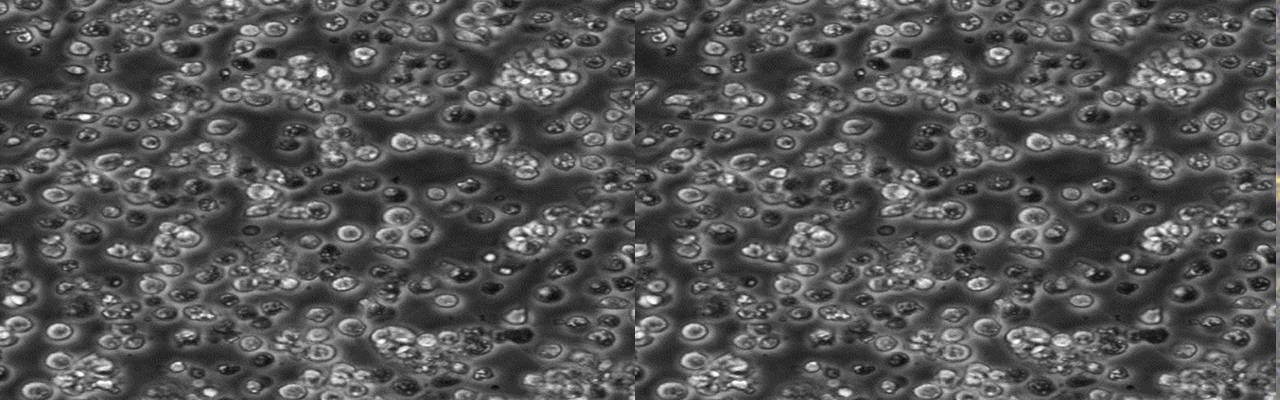

| 细胞全名 | Reh(人急性非B非T淋巴细胞白血病) |

| 生长特性: | 悬浮 |

2)75%酒精消毒瓶身后放培养箱中静置4-6h后,在显微镜下确认细胞状态并拍照100倍和200倍的照片,若有贴壁细胞脱落,可收集上清离心,将沉淀用新的培养基接种至新的培养瓶或培养皿中。